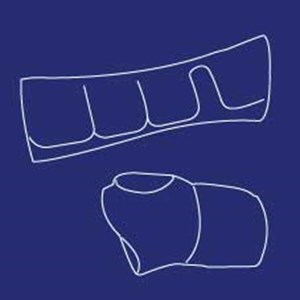

Halskraver

Type: pdf

Størrelse: 1003 KB